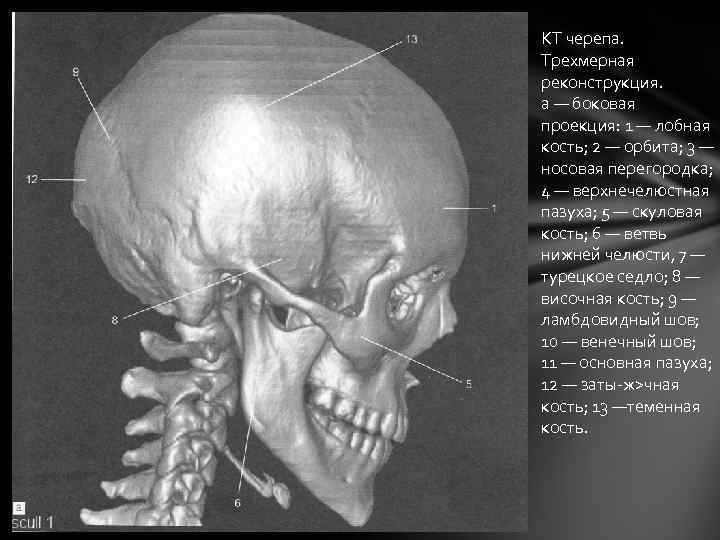

Анатомия детского черепа: Рентгеновские снимки и описание